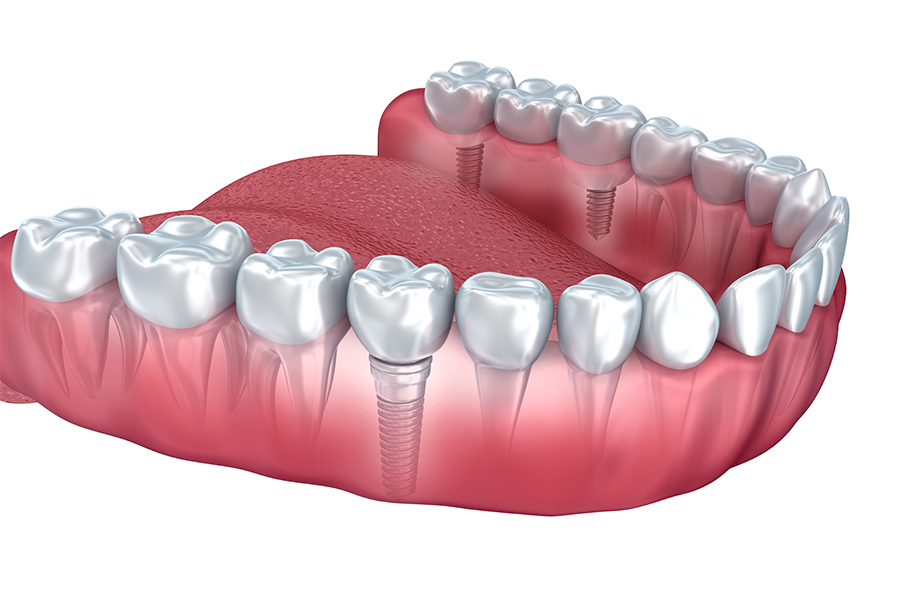

永久歯が2度生えればよいのに・・・』と思ってことはありませんか?永久歯がなくなってしまった時に、今までは、取り外しができる義歯や隣の歯を削って欠損している部位を補うブリッジが一般的に使われていました。

今日では、インプラント治療がかなり一般的になってまいりました。世界で初めてインプラント治療は、スウェーデンのPIブローネマルク先生によって1965年に行われ、その患者さんのインプラントは現在も全く問題なく機能しているそうです。

欧米では、すでに確立した安全な術式として、多くの患者さん、歯科医師に支持されています。

インプラント治療の流れ

一次手術

局所麻酔をし、歯肉を切開します。

歯槽骨にインプラント体より少し小さめの穴をあけ、その穴にインプラントを埋入します。

埋入したインプラントに歯肉をかぶせた状態で縫合すれば、一次手術終了です。

治癒期間

インプラントと骨が結合するまで約3ヶ月から長い方で6ヶ月間待ちます。

この間に、インプラントの素材であるチタンと骨とがしっかりと結合し、自分の歯でいう、歯根と同じような役割を果たせるようになります。

2次手術

人工の歯を取り付ける準備をします。

局所麻酔をして歯肉を切開しアパットメントを取り付けます。切開した歯肉を縫合すれば二次手術終了です。

この状態で、歯ぐきが治るまで1~6週間おきます。二次手術を行わない1回法の手術法もあります。

人工歯冠の作成

歯肉が治った時点で型を取り、人工の歯を作ります。

形や色などは患者さんに合わせて作製し、インプラントにスクリューで固定します。

噛み合わせの調整をして完了です。

インプラントへの固定は、人工の歯をセメントにより固定する方法もあります。